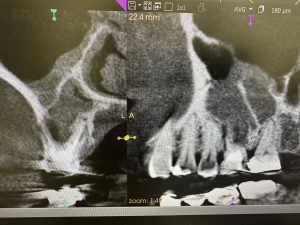

意図的抜歯、掻爬し再植症例はなかなか無い

前歯か小臼歯に限定

外科処置、抜歯時に破折危険無い症例はなかなか少ない

今は、ヤグレーザーあるから、嫌われる外科処置しなくても3〰︎4カ月で骨化し咀嚼可能、後はMTAセメントやら自然治癒力で治ります

どちらが良いかは、もう少し吟味、比較検討する